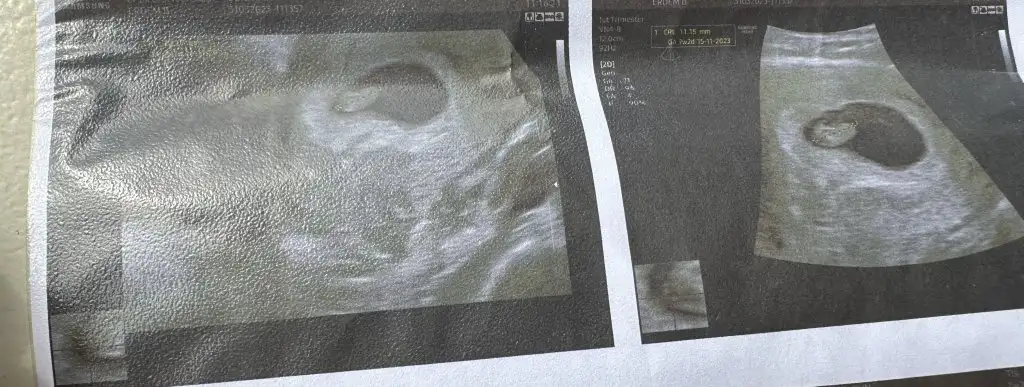

Bende ilk ultrason muayenesi oldun nasip olursa kasima anne adayiyim. Kese gordu ama bebek yok 6+6 dayiz ama bebek olusuma baslamis cikintisi var dedi

Eki Görüntüle 3226041

Bende salı keseyi gördüm 10 mmdi 15 gün sonra gel dedi doktor inşallah görürüm bebişi

16 Kasım dedi benim için de kalp atışını duyduk bugün 7+1 haftalık - cinsiyet için bi yorumda bulunabilir misiniz